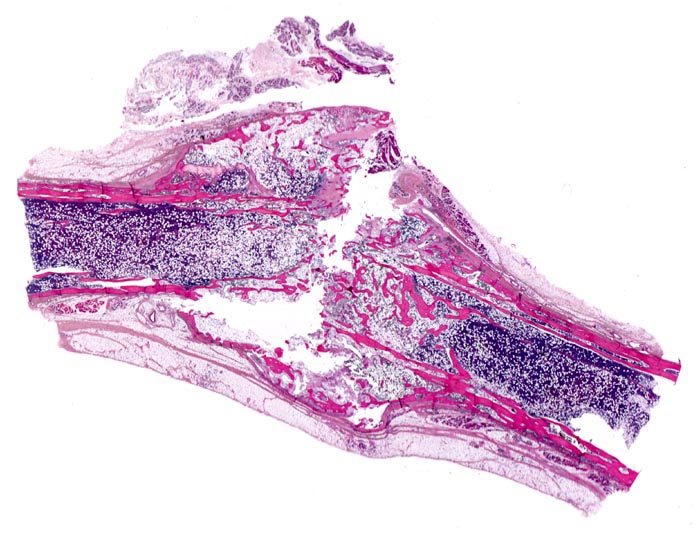

PathoPic – image database / PathoPic ID 5142 - Osteogenesis imperfecta

Osteogenesis imperfecta

Knochen, Rippe

Alte Rippenfraktur mit knöchernem Frakturkallus und knöchernem Durchbau des Frakturspaltes. Die Kortikalis ist extrem dünn und die Spongiosa ausserhalb der Frakturzone zeigt eine ausgeprägte Osteopenie.

Tod an Rechtsherzversagen bei Cor pulmonale. Multiple, zum Teil nicht ganz frische Frakturen vorwiegend der Rippen mit ausgeprägter Deformierung des Thorax und des übrigen Skeletts. Generalisierte Osteopenie. Kyphoskoliose. Multiple Knochenmarkembolien der Lunge.

Glasknochenkrankheit, pulmonale arterielle Hypertonie